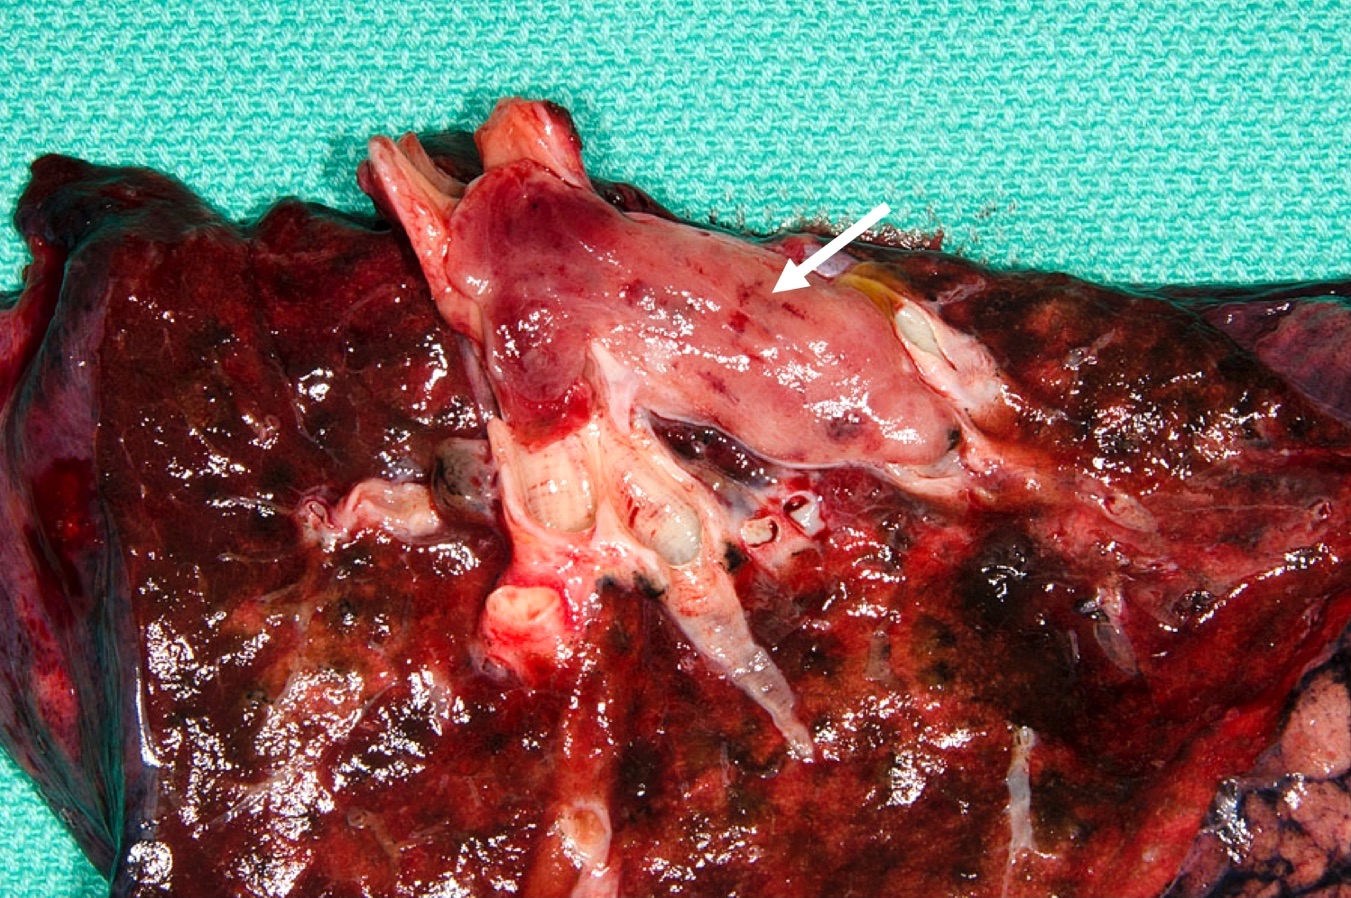

Gross description

- Well circumscribed, round to oval tan colored tumors

- Localization

- Frequently in bronchial lumen, sessile or pedunculated with partial or complete obstruction of the lumen

- Peripheral tumors may not be evidently located in airways

- Size range: 0.5 - 9.5 cm

- Reference: Lung Cancer Int 2015;2015:545601

Gross images